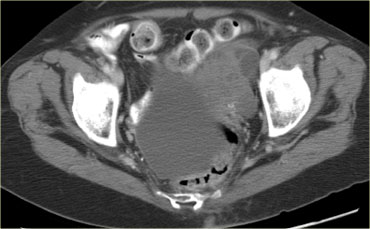

Trên siêu âm, cả hai buồng trứng đều to rõ rệt và chứa các thành phần nang với các thành phần đặc trong lòng nang (mũi tên).

Các tổn thương đặc-nang phức tạp, kết hợp với tính chất hai bên, rất nghi ngờ cho u nang buồng trứng thực sự và cần được đánh giá thêm.

Một lần nữa, vai trò của chẩn đoán hình ảnh là xác nhận sự hiện diện của tổn thương và kết luận rằng đây không phải là tổn thương có thể được phân loại chắc chắn là lành tính, cũng không phải là tổn thương có thể theo dõi an toàn: cần phải có hành động can thiệp.

CT của cùng bệnh nhân xác nhận các tổn thương đặc-nang phức tạp hai bên kích thước lớn, phồng vào ổ bụng.